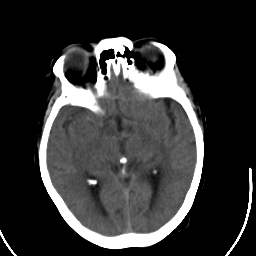

Stroke CT #2 -- Slice #11

[Home][Help][Clinical] Slice 11